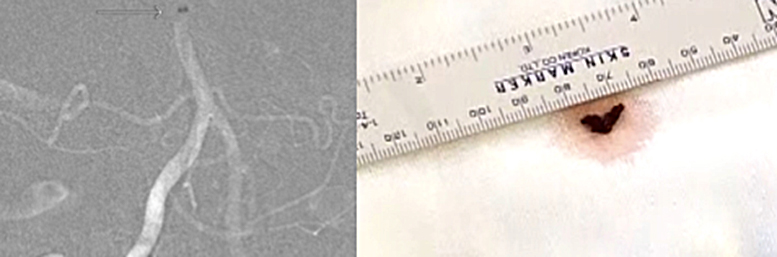

一つは“ステント”と呼ばれる金網を用いる方法、もう一つは“吸引カテーテル”と呼ばれる、文字通り血栓を吸引して除去する方法があります。

ステントは心筋梗塞や狭心症の時に細くなった心臓の血管を広げる時に使われているものとして知られております。ただ、血栓回収療法の時は少し違った使い方をします。血栓で詰まったところでステントを広げると、ステントが広がり血栓を押しつぶします。すると一時的に脳の血流が再開します。ただ、このまま様子をみるとステントの金網の中に血栓がめり込みます。そのうちめり込んだ血栓により再度血管が詰まってしまいます。これでは意味が無いのでは、と思ってしまいますが、再度詰まることでステントが血栓に絡んだと判断できます。そうすれば、このステントをゆっくり引くとステントに絡んだ血栓も一緒に引けて来て、ステントを抜去すると血栓も取り除くことができます。うまくいけば、1回で詰まった血栓を除去できます。